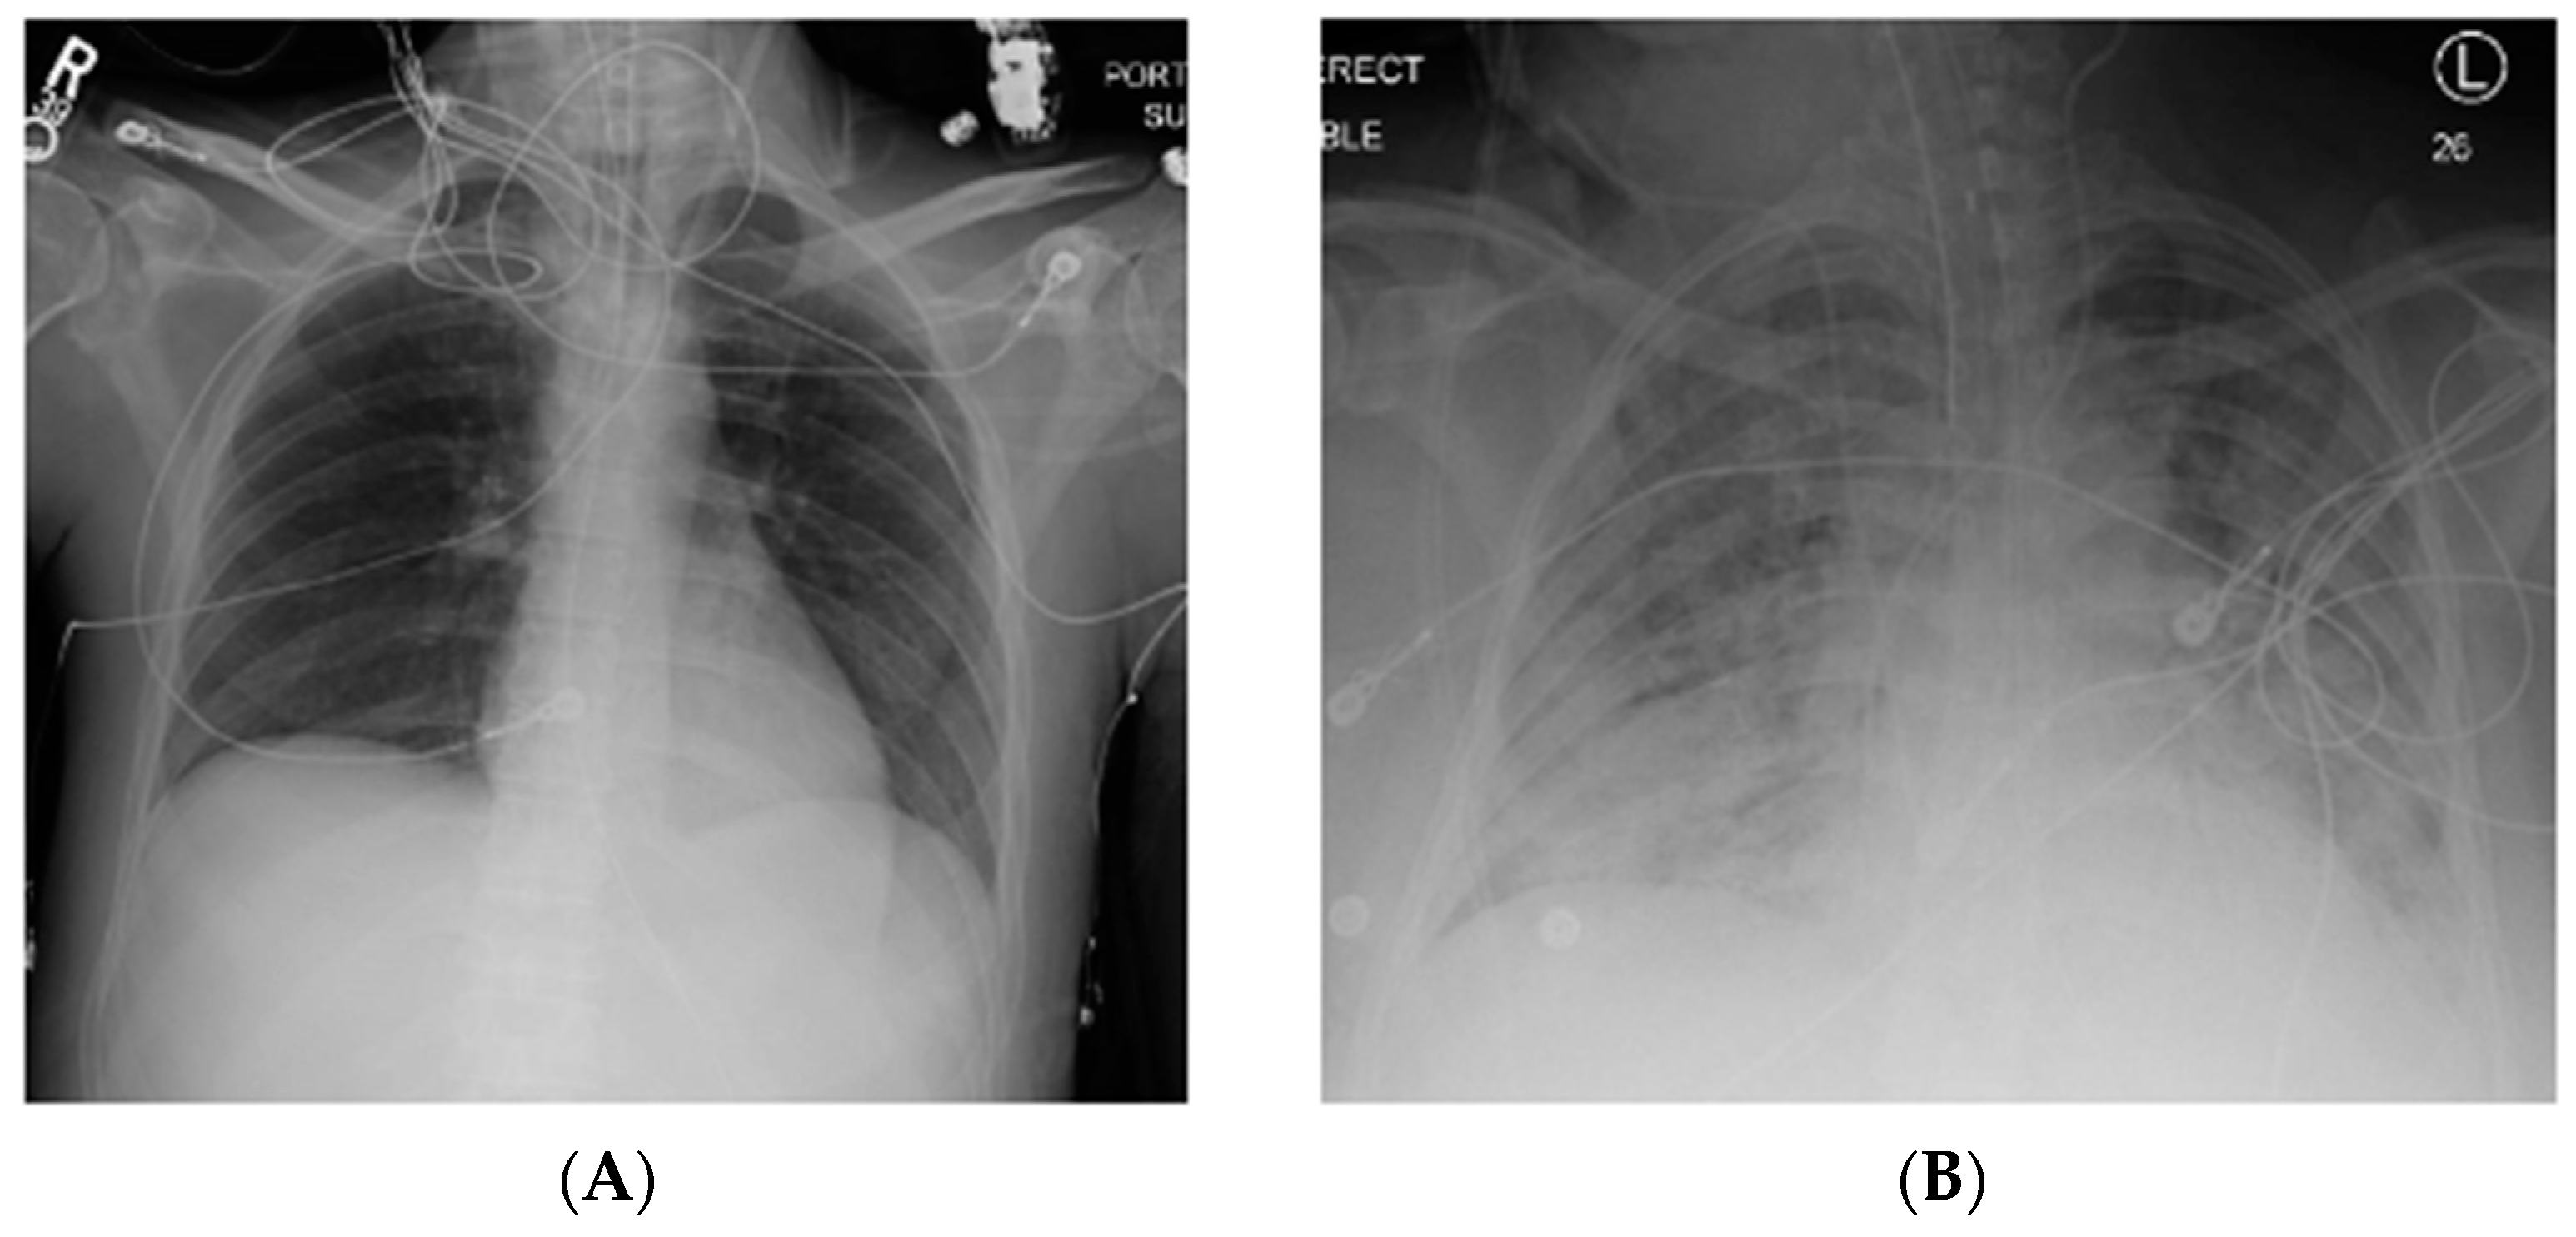

Acute respiratory distress syndrome (ARDS) is a severe, life-threatening form of acute lung injury characterized by inflammation, lung permeability, and edema [1,2,3]. Clinical sequelae include significant hypoxia and bilateral infiltrates on chest imaging (Figure 1) [4]. Since the original description by Ashbaugh in 1967, significant advances have been made in the understanding of this disease process [2,5]. However, this syndrome remains common, and is associated with significant morbidity and mortality [1].

Figure 1.

Normal chest X-ray (A) compared to that of a patient with acute respiratory distress syndrome (ARDS) (B) with bilateral pulmonary infiltrates. R, right; L, left.

Diagnostic criteria of ARDS rely on imaging and other clinical findings. The most recent definition, the Berlin Definition (Table 1), deviates from the previous division of acute lung injury (ALI) and ARDS [6]. Instead, mild, moderate, and severe ARDS severity categories are described based on the PaO2/FiO2 ratio. Additional tenants include respiratory failure not explained by fluid overload or cardiac failure, characteristic imaging findings (Figure 1), and origin of onset within 7 days of symptoms or known clinical insult [6]. Most common etiologies of ARDS include sepsis, pneumonia, and aspiration, but a number of other less common risk factors exist (Table 2) [1,2]. In addition, new pathogens may emerge that manifest in ARDS, such as the novel coronavirus disease 2019 (COVID-19) [7].